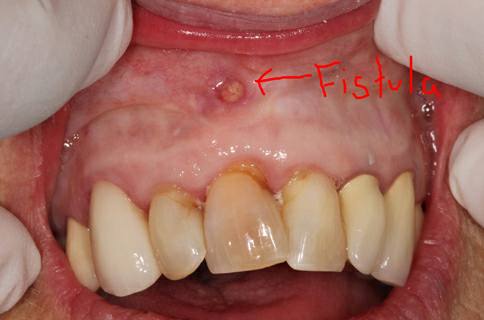

Gusi Bengkak Bernanah Segera Atasi Dengan Cara Ini Sebelum Terlambat Harapan Rakyat Online

Gigi Rongak Jadi Punca Muncul Benjolan Kecil Bernanah Di Gusi Mingguan Wanita